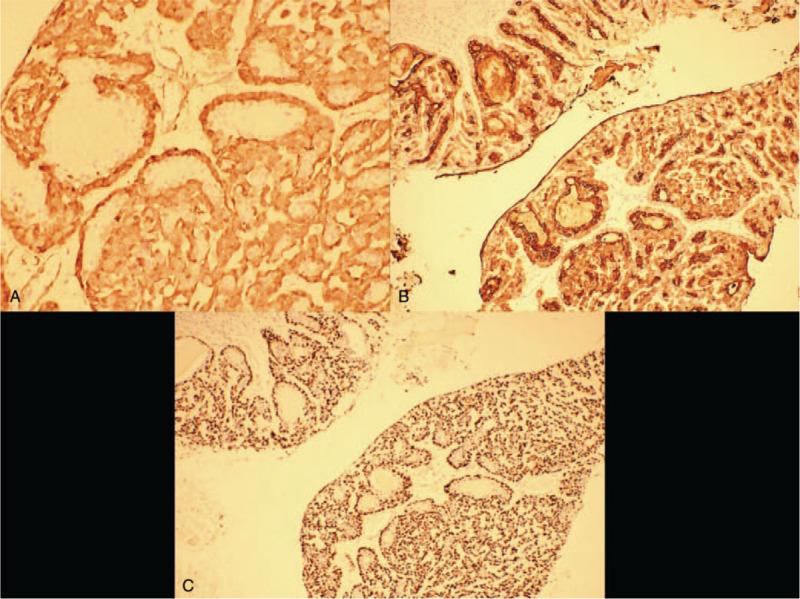

乳腺恶性腺肌上皮瘤:一例报告。

Malignant adenomyoepithelioma of the breast: A case report.

RATIONALE

Adenomyoepithelioma (AME) is a rare biphasic tumor consisting of epithelial and Myoepithelial cell. Most of the AME is benign, and only a few will progress to malignancy, Here, we report a case of low-grade malignant adenomyoepithelioma, and review the related literature, in a bid to investigate its clinical and pathological features and thus, enhance our understanding of this tumor.

DIAGNOSIS

Histological examination confirmed the diagnosis of malignant adenomyoepithelioma.

腺肌上皮瘤(AME)是一种由上皮和肌上皮细胞组成的罕见双相性肿瘤。大多数 AME 为良性,仅有少数会进展为恶性。在此,我们报告一例低级别恶性腺肌上皮瘤,并复习相关文献,旨在探讨其临床和病理特征,从而加深对该肿瘤的认识。

组织学检查证实为恶性腺肌上皮瘤。